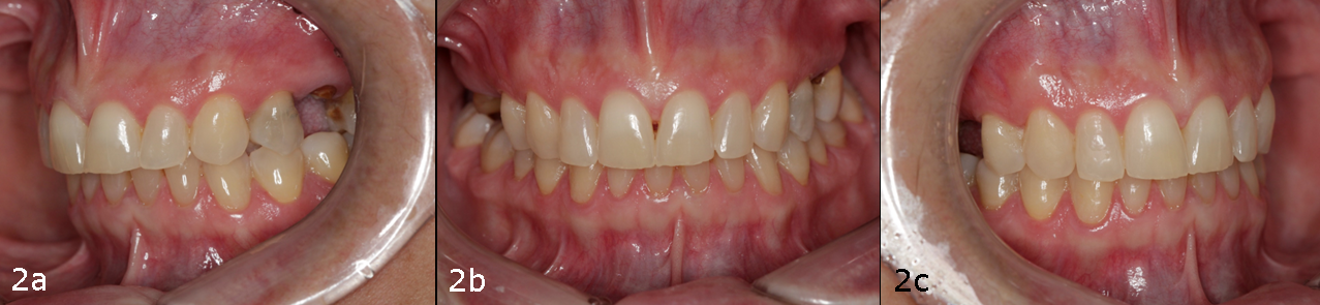

A 38-year-old female patient presented to the dental office reporting social discomfort when smiling, owing to the absence of both maxillary second premolars (Figs. 1a– c, Figs. 2a–c & 3). Clinical examination revealed that tooth #16 had an intra-radicular post and had been prepared for a crown, but the crown was missing, and a cavity was noted on the distal surface of tooth #14. Overall, the patient exhibited a healthy periodontal condition. She was a non-smoker and did not present with any comorbidities or systemic health issues. CBCT imaging showed adequate bone quality and quantity at both sites and no signs of acute infection. Additionally, a residual root was identified at site #15 beneath the already healed gingiva.